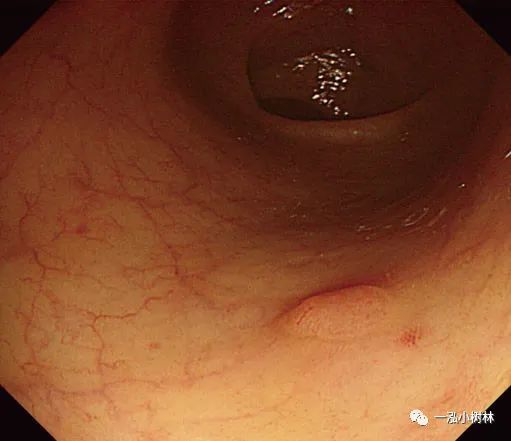

例5 小息肉冷圈套切除术

图片

图5a 横结肠处4mm大小0-IIa型腺瘤

图5b 在病灶上方圈套

图5c 圈套包括病灶周围1-2mm正常黏膜

图5d 对病变进行机械性横切

图5e 对病变进行机械性横切

图5f 息肉取出后出血

图5g 黏膜出血止血

图5h 可见息肉边缘正常黏膜的标本